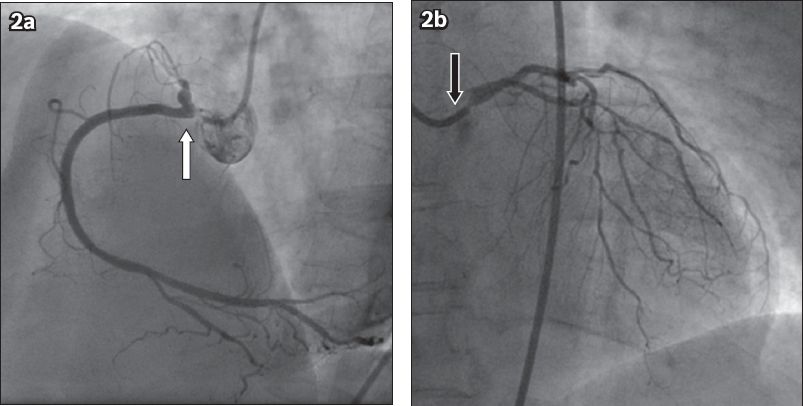

In view of her symptoms and abnormal treadmill ECG stress test, the patient underwent coronary angiography, which showed severe left main and triple vessel disease. She had 90% ostial left main stenosis, severe diffuse distal disease in the left anterior descending (LAD) and circumflex arteries, as well as 90% ostial right coronary artery (RCA) stenosis with 70% stenosis in the posterior descending artery (

Fig. 2

Coronary angiograms show (a) 90% stenosis in the ostium of the right coronary artery (white arrow) in the left anterior oblique view; and (b) 90% stenosis in the ostium of the left main coronary artery (black arrow) with diffuse disease in the left anterior descending and left circumflex artery in the right anterior oblique cranial view.